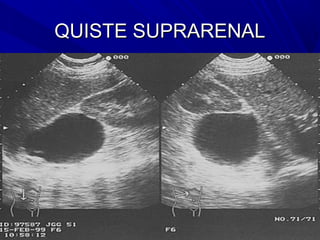

QUISTE SUPRARENAL